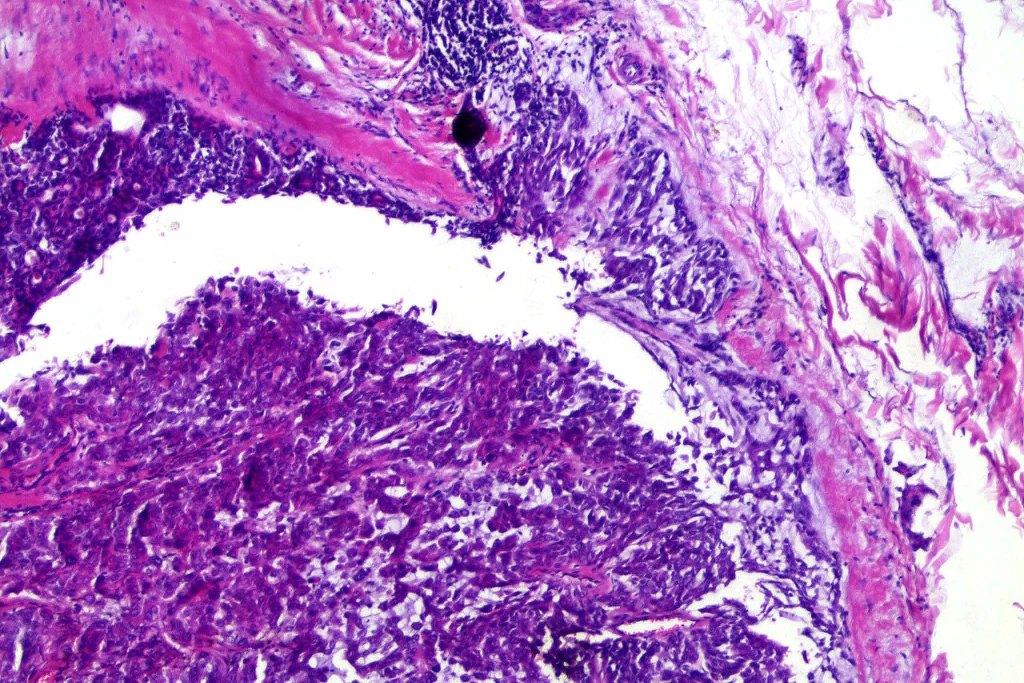

•Well circumscribed unencapsulated, nodular/multinodular silhouette composed of an admixture of epithelial & mesenchymal elements

•Glandular differentiation sometimes showing apocrine differentiation

•Myoepithelial layer in glandular foci

•Ductal differentiation

•Stromal sclerosis & hyalinization

•Myxoid change

•Chondroid foci